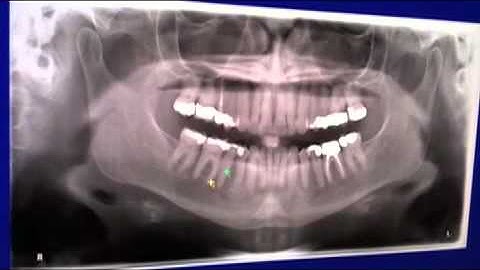

How to use the Veraviewepocs 3D - CBCT - Operation Video